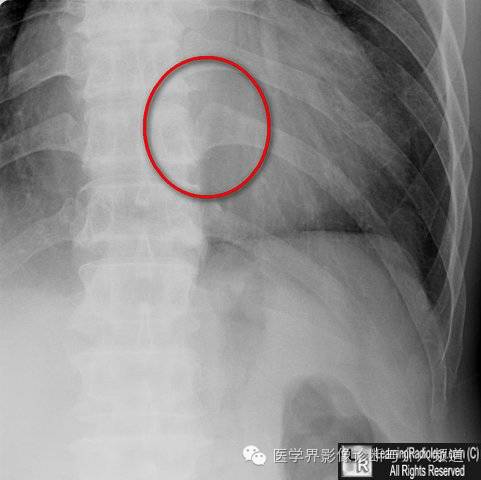

16、椎肋关节:勿把正常的椎肋关节误认为骨折线。